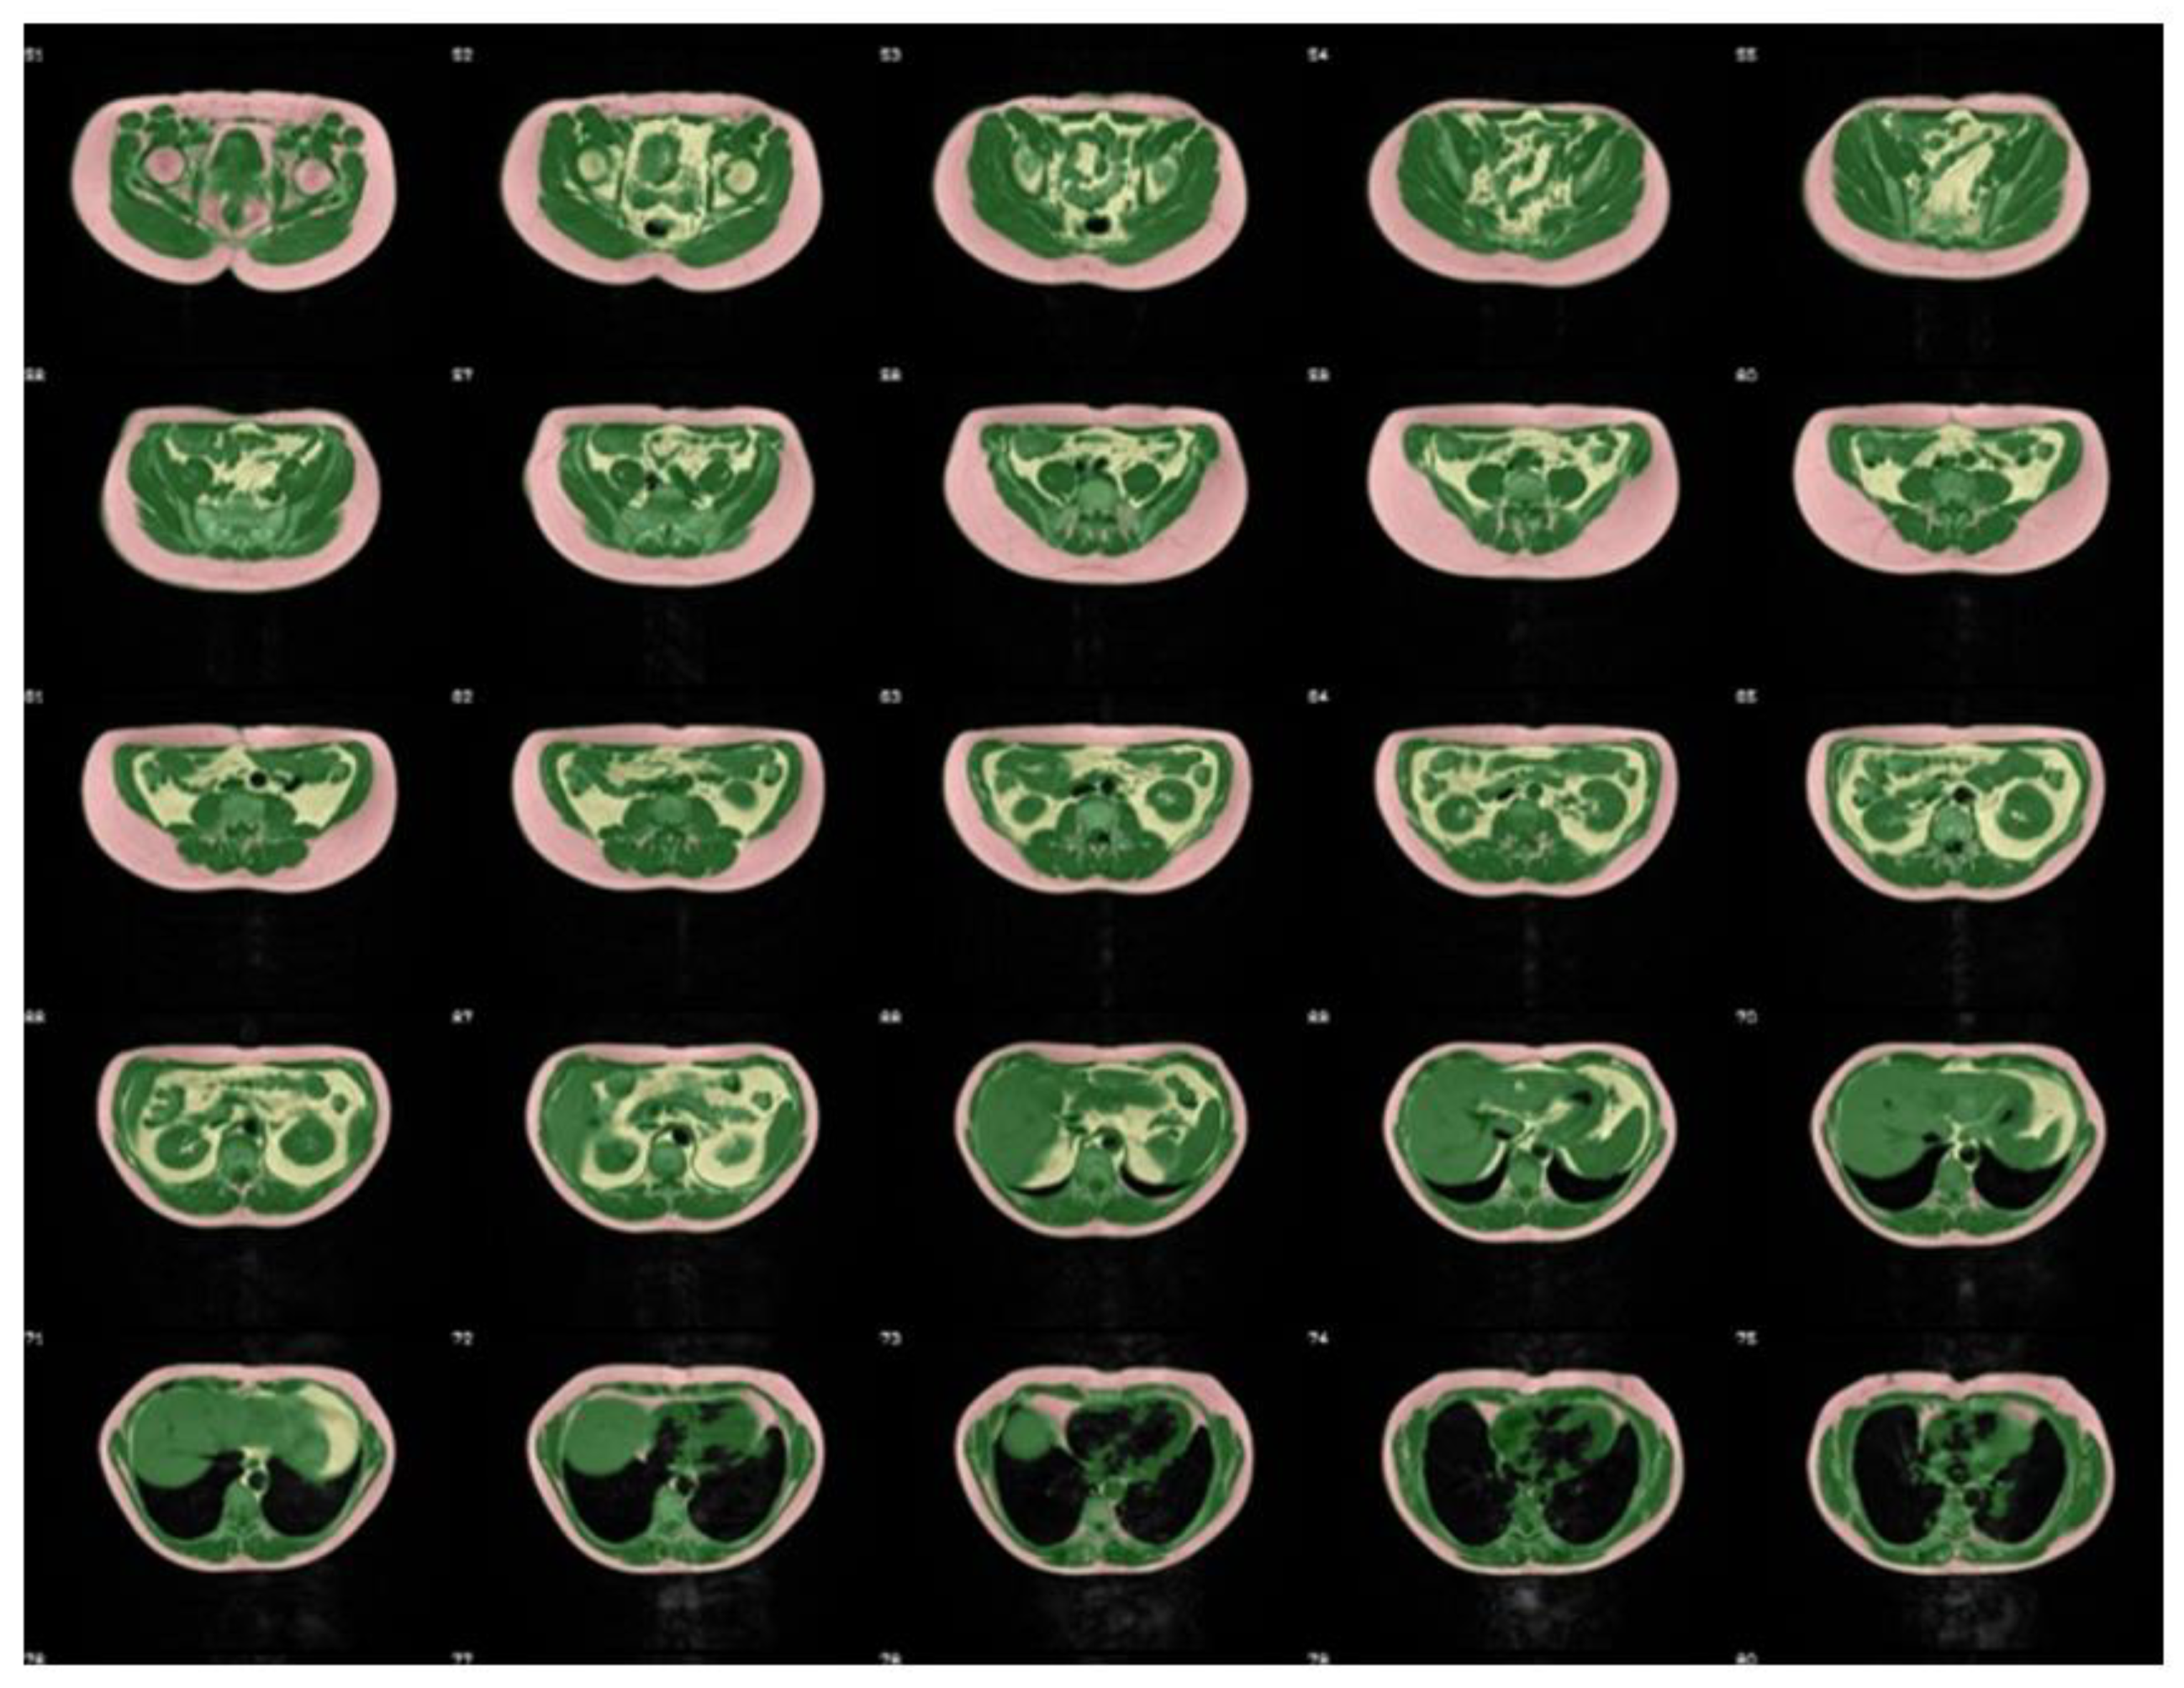

2.1. Magnetic Resonance Imaging